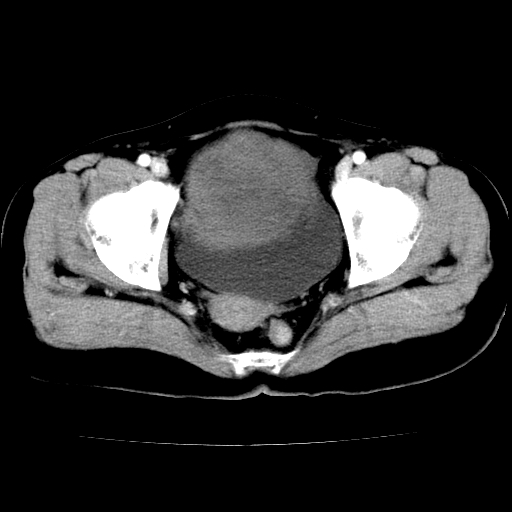

标题: CT24785:女,62岁,发现下腹部肿物半年。 [打印本页]

标题: CT24785:女,62岁,发现下腹部肿物半年。

女,62岁,发现下腹部肿物半年,下腹部不适。

该年龄性别首先考虑平滑肌肉瘤可能性大,其他待排除。

考虑子宫平滑肌肉瘤可能性大。

实性成分太多,要是囊腺瘤也要考虑恶性。